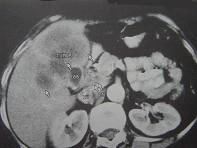

问题 患者,女,51岁,右上腹隐痛1月余,CT扫描如图,最可能的诊断是()

选项 A.胆囊癌(肿块型)侵犯肝脏 B.肝癌侵及胆囊 C.肝转移瘤 D.胆囊周围肝脓肿 E.肝血管瘤

答案 A